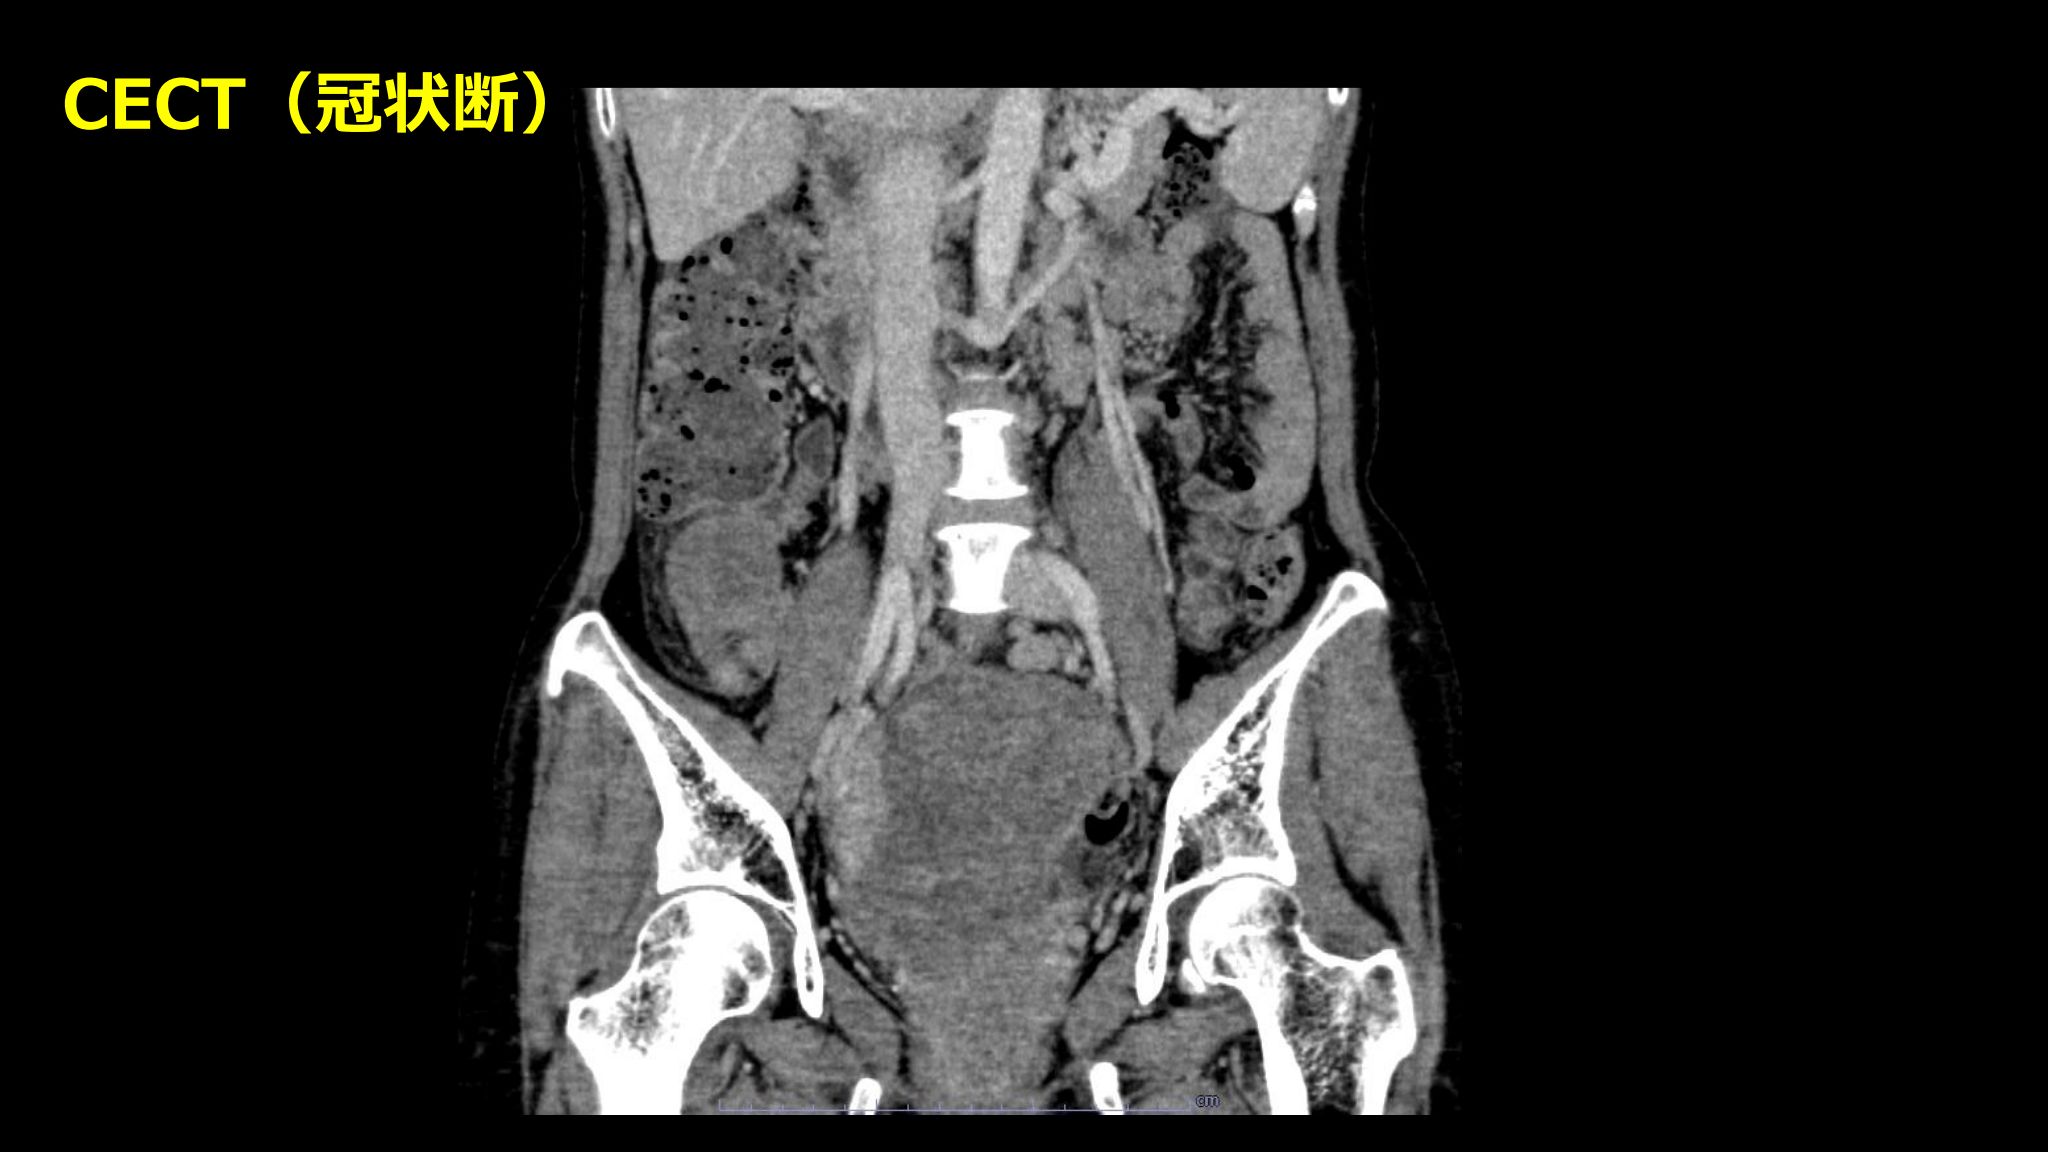

| 症例 | 50歳代女性 |

| 主訴 | 排尿困難 |

| 現病歴 | 3カ月前から排尿困難を自覚した 腹部超音波検査を施行され、子宮筋腫疑いにて紹介受診となった |

| 既往歴 | 5年前より原因不明の肝障害が持続しているとのこと 他、特記すべき既往なし |

| 身体所見 | 腹部腫瘤を触知するほか特記すべき事項なし |

| 補足情報 | 骨盤部の最大の病変は両側卵巣腫瘤であった 術前の上下部内視鏡検査では消化器系の悪性腫瘍を指摘できなかった 膀胱頸部側の病変疑いについても膀胱鏡が施行されたが、 異常を指摘できなかった(今回の病態との関連は不明) |